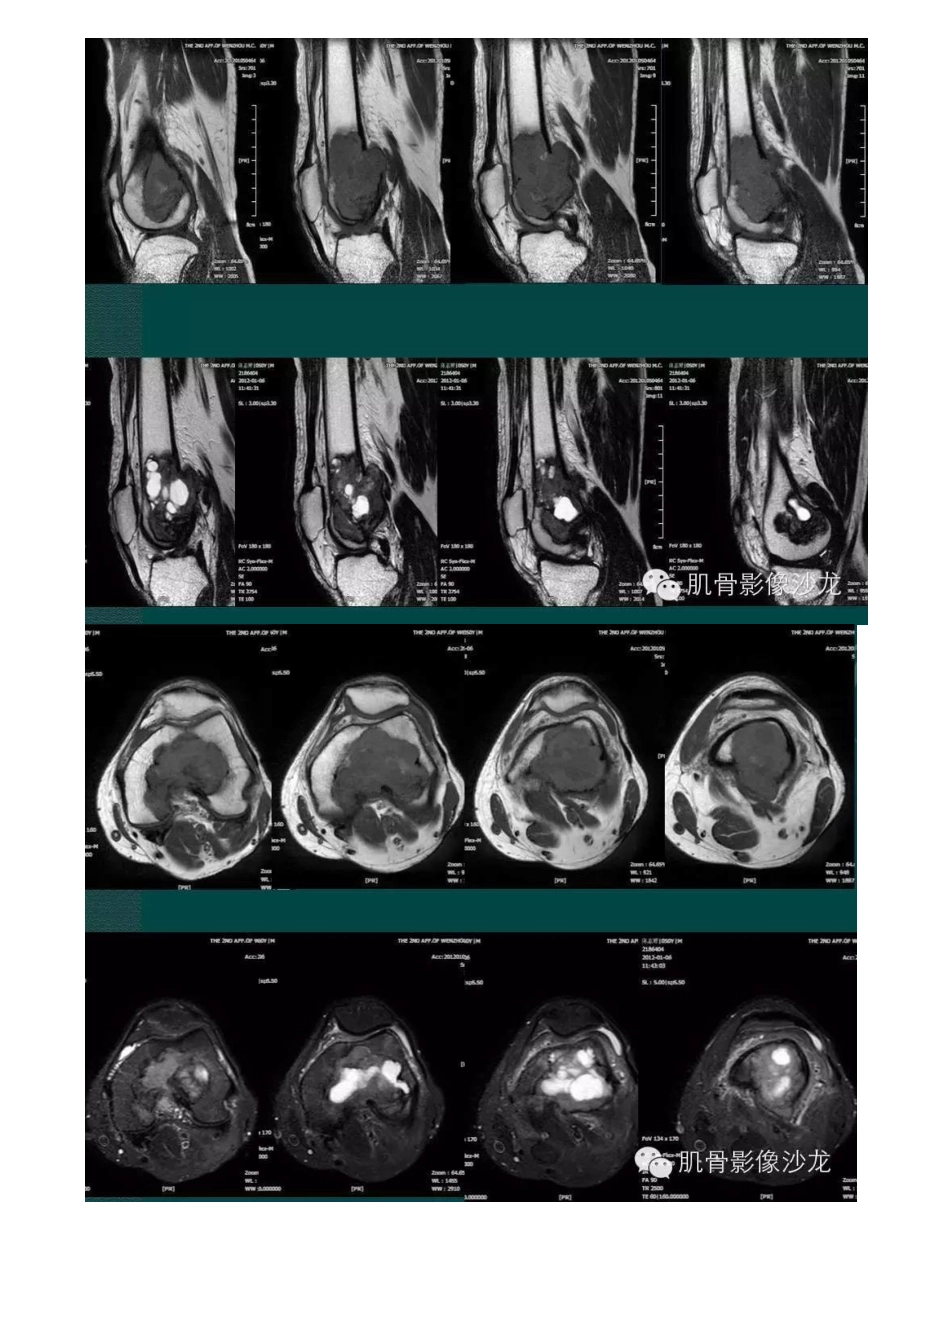

医学影像:良性纤维组织细胞瘤

良性纤维组织细胞瘤良性纤维组织细胞瘤 5 例温州医科大学附二医院陈旺强老师提供病例四女 76 岁月圣骨上端内侧 幌及股骨下 端内侧眼见两个病灶 ,其 边缘洁 H 析锐利 ,未见明显 硬化边 。;币以,部 分细胞有轩)立异 'l ,未见 明 M 而 坷,’性核 分裂反瘤 E 细胞 。 纣合||伍)术及 免疫细化纣 ;叭 ,之··店、为免疫 ffL 化 :Vim( +); CD68 散在(+): SMA(+) ;Desmim(-);CK(-);’叫 l'L 'i" i .? rff L i I.=飞 flll lJ{Q:l\:i' i (benign fibrous histiocytoma,BFH) BFHi1 巳) t L'.l 发 I l:_ J J 之 !川、了: 山 i',JIj 0 f:i1 .1 1Tj 个 1, t J1 1i 三{, ·'/j iii i 虫 |’f \j 21 1. ?'1, ,、 :'f J 1;1J_)Ji!I:J/ii L . .J 「'i'J·i1i\i1) , IIJ f) !{IE 巧 !jt 二 tt L1). '{t ,,↓'J° lf J llr J- 'It { i!. 川、.,LLJ 过 1 1 ··J_'.J·f t tI:二 「 ffL 、以’{ , h\·J Iti I J IJ 己,(1h111..( _1 1 { 、 欠’J.L '?I’j< J j 乏川-f l 让 fr 丑 化 , I ] ·1、见!儿’f J - /之 1tlj f 仁,;, 1 -.. )L,i· 1> 1 乏 h;‘1 1J (uJ ;;i· 1 1 , ll:fY,J !1 :z ,'1 i1||才 . T2W IJ 之 T2W II I : !Jti 1 军 I -.J 斗 i J I ffj 1 ', iJ 1,'; 11J. : 三 L'j )Jrt l.) \ /!1-j1 J J1!1 ·J\:;,{ 1 j 丁 汀 ffr ?1 11 1J@ ) i'i [. 川i/1 1 1 !J 但;'! ;/:{{ 斤 11 工j ’T2W I J 之 T2W l i l、H 订 仅 |1 ,' rn 1 ', ,'1 i\ 1ii 1 ', i J ;'LI :1 川、i ',)1J1t1 怕 Ill。但 1 ! 1 1·主 n:> r ff i: 1:Jf111 1J 问科 l J f l)Jl f.f f'!1 I iJU 1·;'.J1'(1. j:句 l 注 >;+ν!1 1 iJ{Q JiJ i° rJ I 戊 . ? r fft:’I''I:'l'j. 与 )|注 1J Ji'/ l、| | ’i 斗’ (七 t'l·. f 「ht 二 怕 ;BFHJ 斗 1Jtii 才 | {11, t f'l1 1 1HY,丛 I I f'lil IJD,n-1 :J: '·j 11 1 川、了 ’ ti·;人 :J:] 'I!j ,j Ji ! I_ I 个 tit I ,( J :. L iJ}川、J:1BFH 、·J /({ ! iJJ h( ( J ·['j· ['J-;u IJ\:Jt(.'j- 小升飞 1'1 iJ I;ii f I 才,J !'i